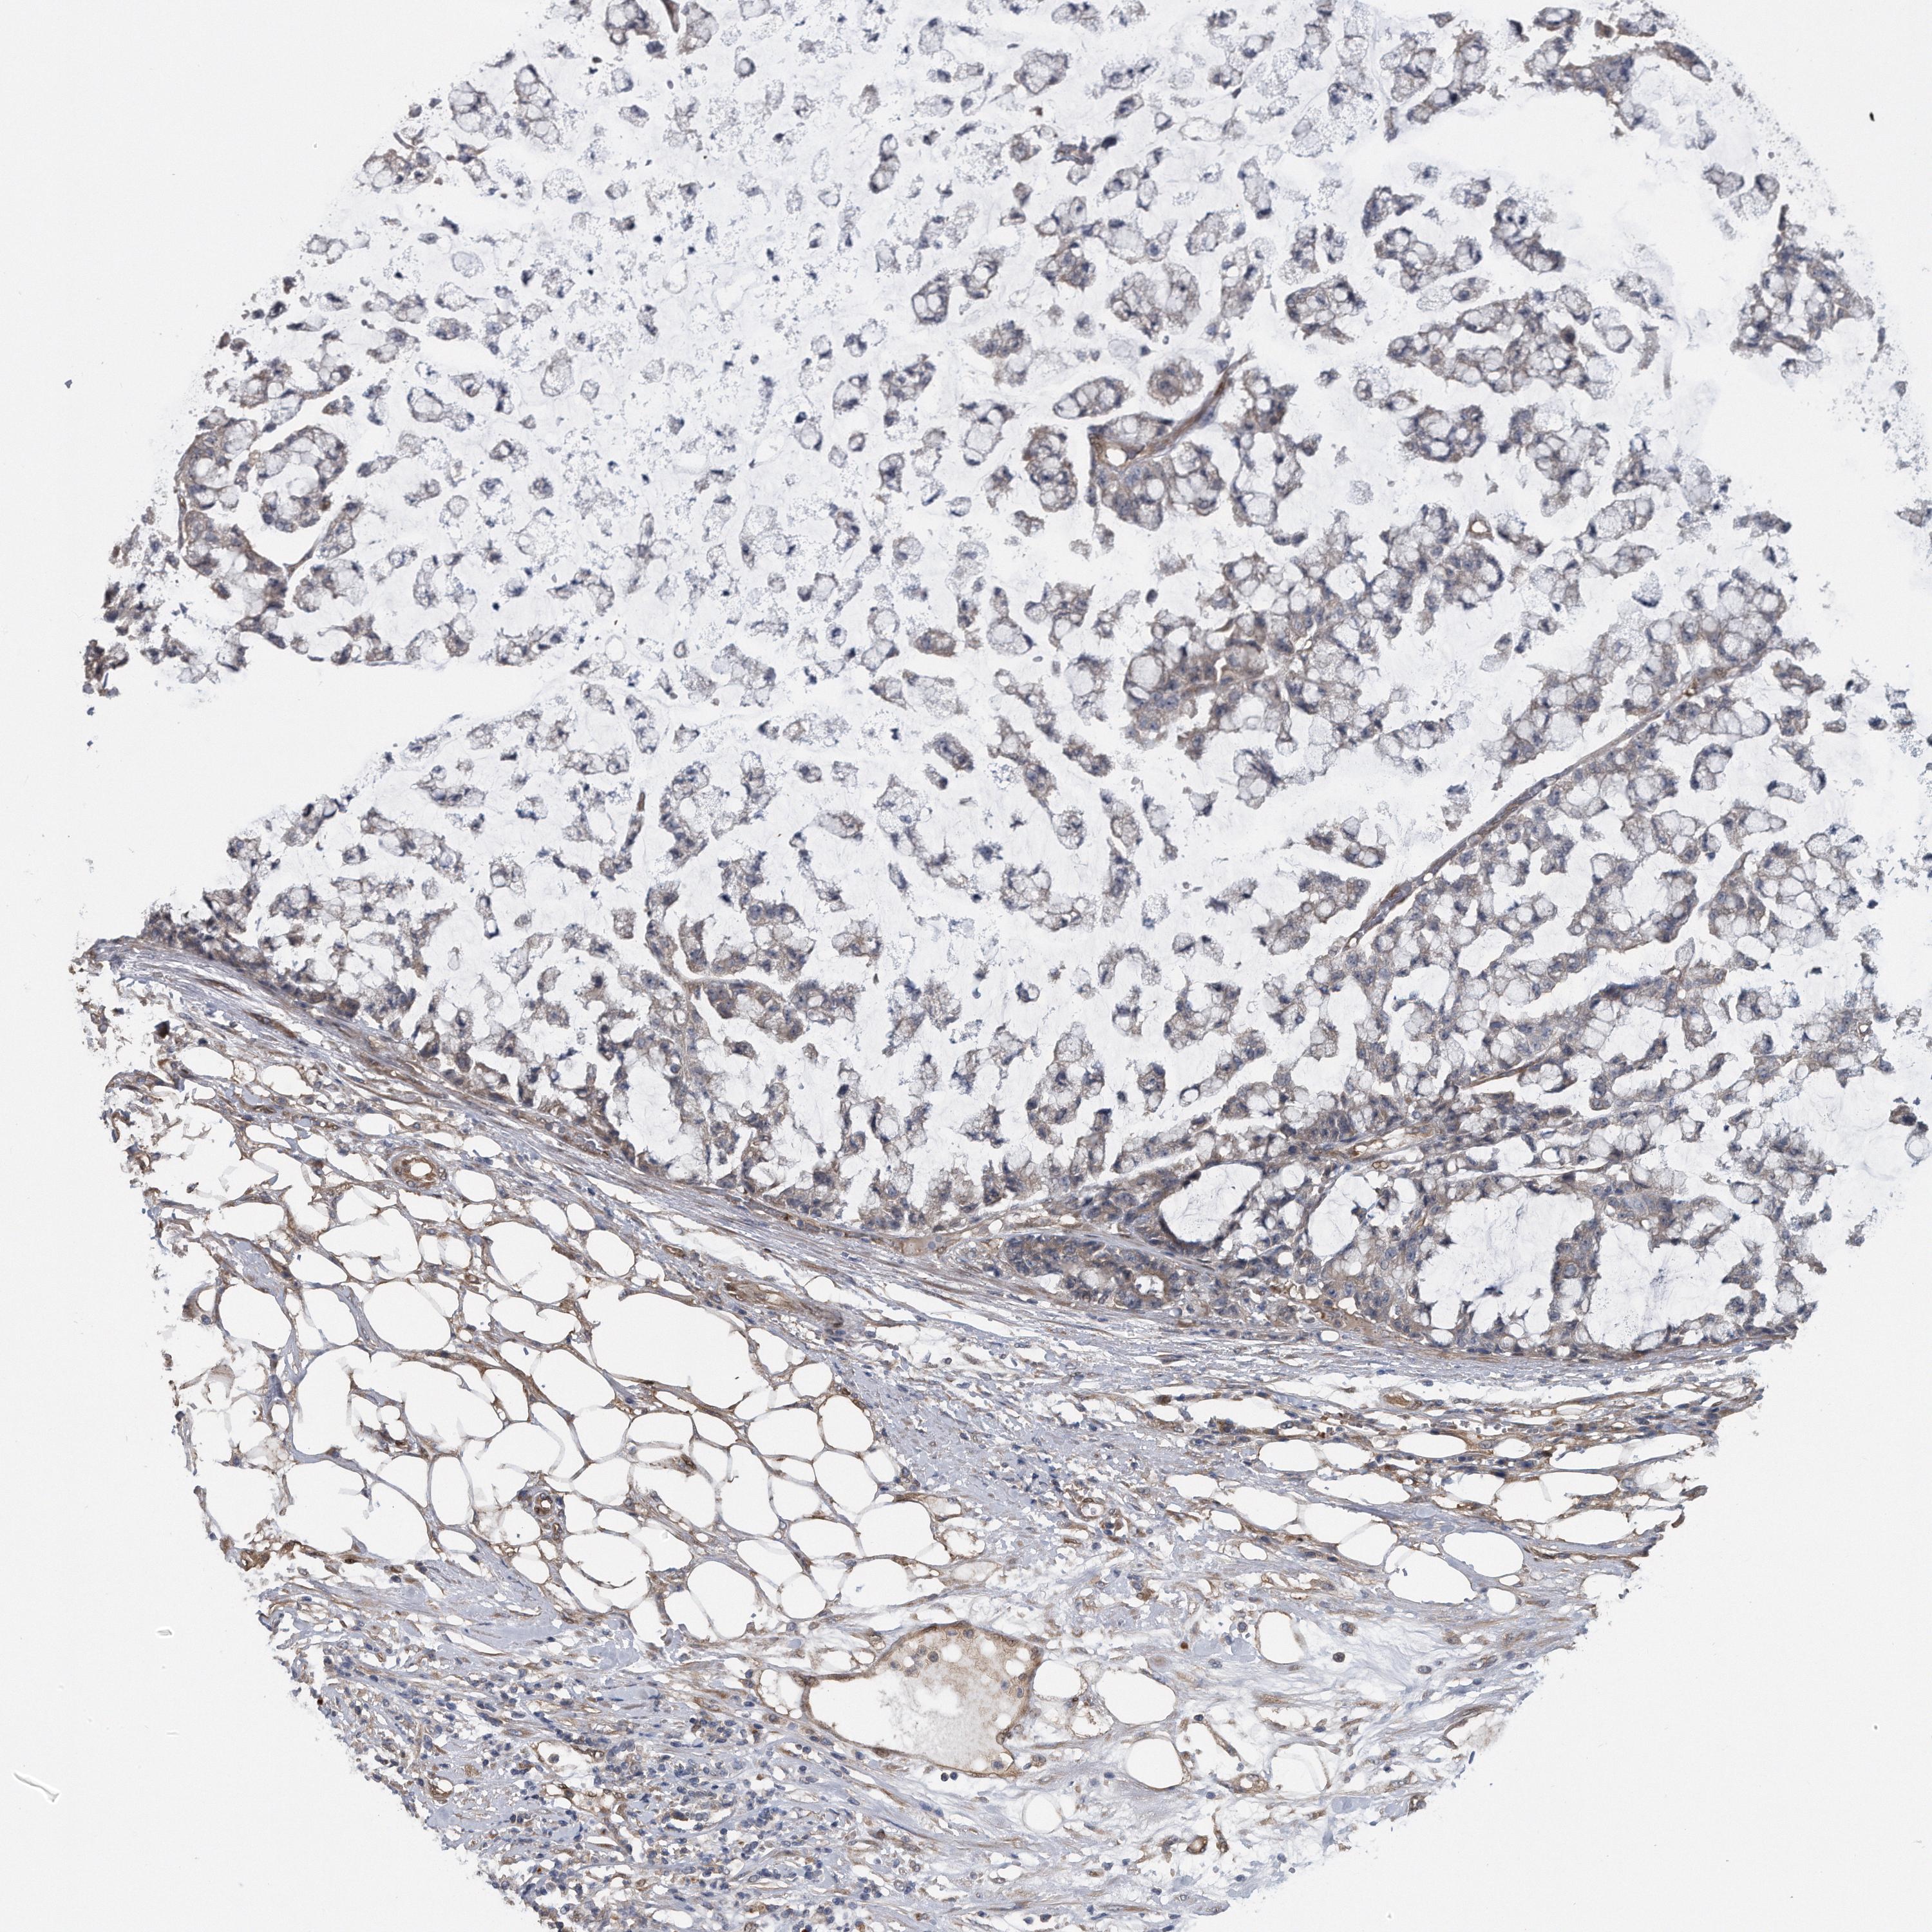

TCGA RNA samplesi

RNA-seq data is reported as average FPKM (number Fragments Per Kilobase of exon per Million reads), generated by the The Cancer Genome Atlas (TCGA) .

Normal distribution across the dataset is visualized with box plots, shown as median and 25th and 75th percentiles. Points are displayed as outliers if they are above or below 1.5 times the interquartile range. FPKM values of the individual samples are presented next to the box plot.

Average pTPM 8.7

Number of samples 207

Samples

Sample Description pTPM